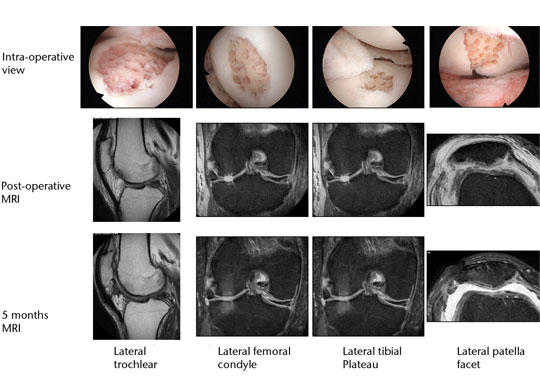

A similar approach can be used in combined chondral injuries and meniscal tears. Figure 2 shows the arthroscopic fi ndings of a 61-year-old orthopaedic surgeon and recreational skier. Two years following injury and after an unsuccessful arthroscopic debridement he was troubled by a persistent knee effusion, limited walking distance and lateral patellar maltracking with chondral lesions over the lateral patellofemoral joint. There was also an associated degenerated lateral meniscus and chondral injury in the lateral compartment. The patient underwent arthroscopic subchondral drilling together with lateral patellar release and subsequently received stem cell therapy. MRI scans at five months showed evidence of repair and regeneration accompanied with clinical improvement.

Fig. 2 Intra-operative views following subchondral drilling with the corresponding MRI scans after surgery and progressive healing at five months of the lateral trochlear, lateral femoral condyle, lateral tibial plateau and lateral patellar facet.